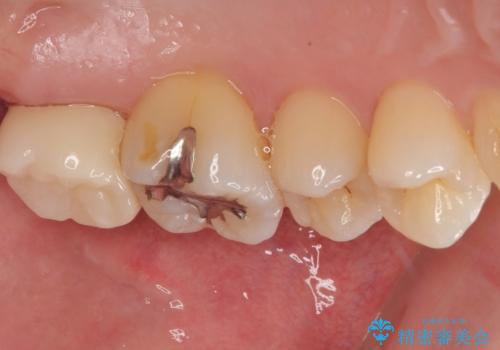

- 元々むし歯があったものの、処置が困難とのことでしたが、矯正治療を終えたので処置をしたいとのことで来院された患者様です。

左右ともに最後臼歯が頬側に顕著に突出しており、むし歯になってしまったことが想像されました。

歯列が移動したとはいえ、左右ともに後方傾斜しており、むし歯の除去、形成(形を整える)、型取りの全てが非常に困難な処置となりました。